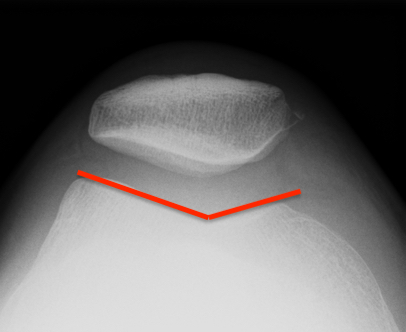

Trochlea Dysplasia / Dejour Crossover Sign

- lateral x-ray at 30o with condyles superimposed

- identify base of trochlea

- normal: clearly defined trochlea groove

- abnormal / Crossover: line of floor of trochlea crosses lateral lip of condyle

Normal trochlea / no crossover